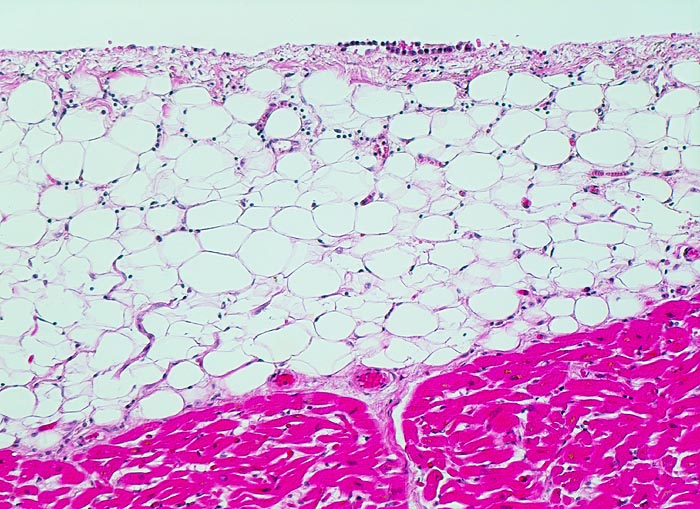

Normales Epikard

Das Epikard bildet das innere viszerale Blatt des Perikards. Auf ein einschichtiges Mesothel folgt ein bindegewebiges subepitheliales Stroma und das epikardiale Fettgewebe. Die Mesothelzellschicht ist nur auf einem kurzen Abschnitt erhalten. Unten im Bild der Herzmuskel.

Histologie

100